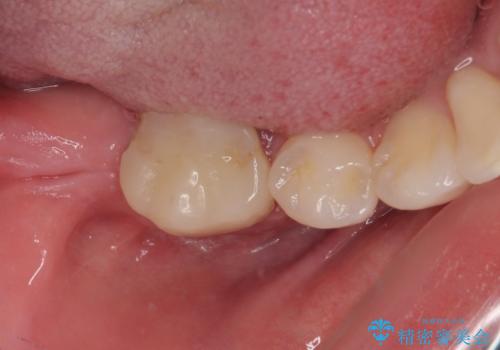

埋伏している右下第二大臼歯は、牽引して咬合に参加させることで計画しましたが、癒着などにより移動困難な場合には、抜歯の上インプラント補綴治療を行うこととしました。

右下の埋伏歯はやはり癒着しており、抜歯の後にインプラントを埋入することとなりました。

埋伏歯の牽引や、奥歯の咬み合わせ改善、インプラント補綴治療と治療期間が延びてしまう要素が多く、治療は難航しましたが、最終的に非常に満足のいく仕上がりとなりました。